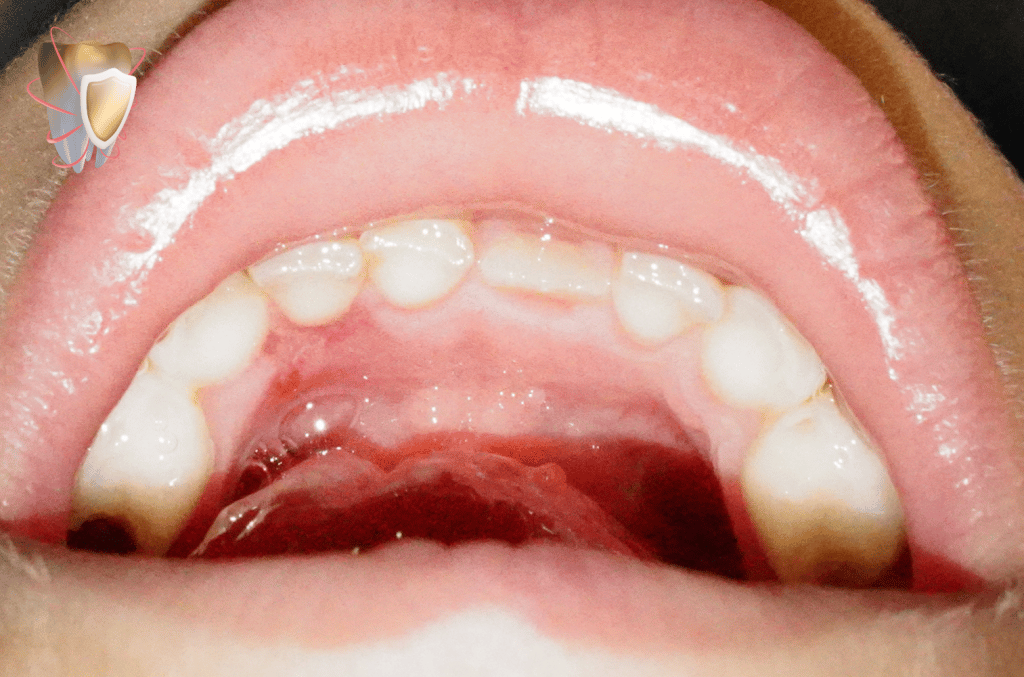

Squamous cell papilloma in 7 years old male patient :-

-irritating 2 white masses causing discomfort related to upper and lower arches.

-Lingual gingiva related to lower deciduous lateral incisor.

– 2 fungating & cauliflower-like masses forming finger like projections .

Duration: upper lesion arised since 9 months , lower lesion arised since 2 months.

Origin: pedunculated.